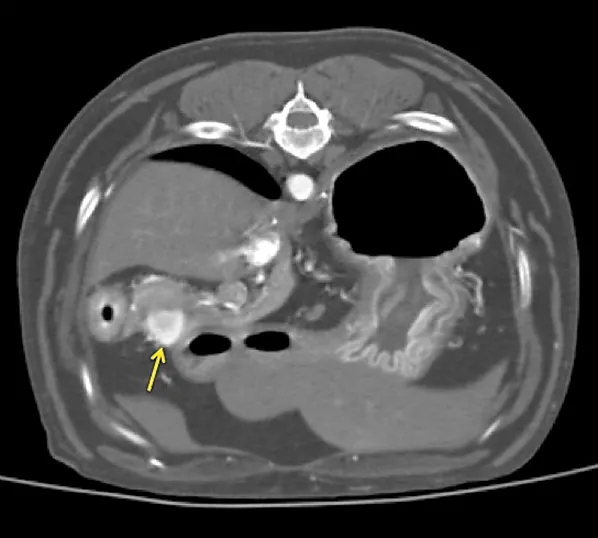

Figure 2 Arterial phase CT angiograph image demonstrating a strongly contrast-enhancing pancreatic nodule (arrow)

A thoracoabdominal dual-phase CT scan was performed with the goals of further evaluating the pancreatic nodule, ruling out obvious metastatic disease, and planning for possible surgery. The CT scan revealed a 1.8 × 2.6-cm nodule in the body of the pancreas that demonstrated marked neovascularization in the early arterial phase and mild peripheral contrast enhancement relative to the remainder of the pancreas in the main arterial and portal phase scans (Figure 2). A strong contrast-enhancing liver nodule was noted in the arterial phase of the CT angiogram (Figure 3). Other hepatic nodules noted on ultrasound were not visualized in the arterial or mixed portal/venous angiographic phases. No evidence of nodular pulmonary metastasis was evident.